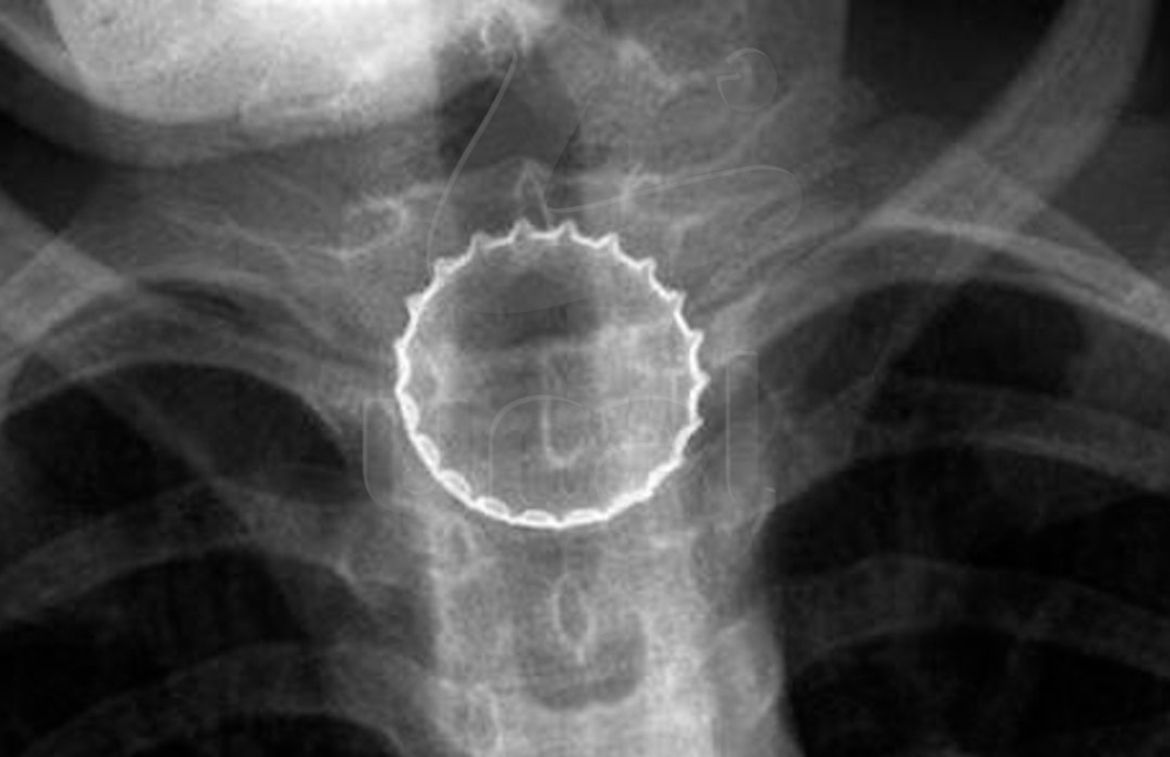

Подросток из Челябинска проглотил металлическую крышку от бутылки.

16-летний школьник поймал железяку губами, та попала в горло и застряла в пищеводе. Потребовалась срочная операция — был риск, что острые края порежут внутренние органы. Хирурги справились, сейчас парень уже дома — со вкусняшками на время придётся расстаться.